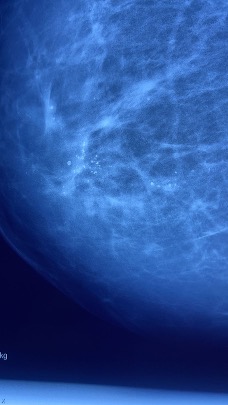

Mastógrafo digital

Mastografía que muestra microcalcificaciones

pleomorficas de alta sospecha de malignidad